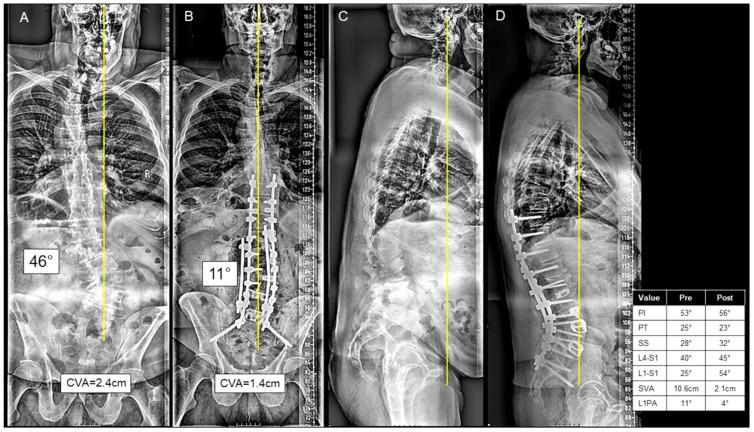

Whether a combined anterior-posterior (AP) approach offers additional benefits over the posterior-only (P) approach in adult spinal deformity (ASD) surgery remains unknown. In a cohort of patients undergoing ASD surgery, we compared the combined AP vs. the P-only approach in: (1) preoperative/perioperative variables, (2) radiographic measurements, and (3) postoperative outcomes. A single-institution, retrospective cohort study was performed for patients undergoing ASD surgery from 2009 to 2021. Inclusion criteria were ≥5-level fusion, sagittal/coronal deformity, and 2-year follow-up. The primary exposure was the operative approach: a combined AP approach or P alone. Postoperative outcomes included mechanical complications, reoperation, and minimal clinically important difference (MCID), defined as 30% of patient-reported outcome measures (PROMs). Multivariable linear regression was controlled for age, BMI, and previous fusion. Among 238 patients undergoing ASD surgery, 34 (14.3%) patients underwent the AP approach and 204 (85.7%) underwent the P-only approach. The AP group consisted mostly of anterior lumbar interbody fusion (ALIF) at L5/S1 (73.5%) and/or L4/L5 (38.0%). Preoperatively, the AP group had more previous fusions (64.7% vs. 28.9%, < 0.001), higher pelvic tilt (PT) (29.6 ± 11.6° vs. 24.6 ± 11.4°, = 0.037), higher T1 pelvic angle (T1PA) (31.8 ± 12.7° vs. 24.0 ± 13.9°, = 0.003), less L1-S1 lordosis (-14.7 ± 28.4° vs. -24.3 ± 33.4°, < 0.039), less L4-S1 lordosis (-25.4 ± 14.7° vs. 31.6 ± 15.5°, = 0.042), and higher sagittal vertical axis (SVA) (102.6 ± 51.9 vs. 66.4 ± 71.2 mm, = 0.005). Perioperatively, the AP approach had longer operative time (553.9 ± 177.4 vs. 397.4 ± 129.0 min, < 0.001), more interbodies placed (100% vs. 17.6%, < 0.001), and longer length of stay (8.4 ± 10.7 vs. 7.0 ± 9.6 days, = 0.026). Radiographically, the AP group had more improvement in T1PA (13.4 ± 8.7° vs. 9.5 ± 8.6°, = 0.005), L1-S1 lordosis (-14.3 ± 25.6° vs. -3.2 ± 20.2°, < 0.001), L4-S1 lordosis (-4.7 ± 16.4° vs. 3.2 ± 13.7°, = 0.008), and SVA (65.3 ± 44.8 vs. 44.8 ± 47.7 mm, = 0.007). These outcomes remained statistically significant in the multivariable analysis controlling for age, BMI, and previous fusion. Postoperatively, no significant differences were found in mechanical complications, reoperations, or MCID of PROMs. Preoperatively, patients undergoing the combined anterior-posterior approach had higher PT, T1PA, and SVA and lower L1-S1 and L4-S1 lordosis than the posterior-only approach. Despite increased operative time and length of stay, the anterior-posterior approach provided greater sagittal correction without any difference in mechanical complications or PROMs.

在成人脊柱畸形(ASD)手术中,前后联合(AP)入路是否比单纯后路(P)入路具有更多优势仍不明确。在一组接受ASD手术的患者中,我们比较了AP联合入路与单纯P入路在以下方面的情况:(1)术前/围手术期变量;(2)影像学测量;(3)术后结果。对2009年至2021年接受ASD手术的患者进行了一项单机构回顾性队列研究。纳入标准为≥5节段融合、矢状面/冠状面畸形以及2年随访。主要暴露因素是手术入路:AP联合入路或单纯P入路。术后结果包括机械性并发症、再次手术以及最小临床重要差异(MCID),MCID定义为患者报告结局量表(PROMs)的30%。多变量线性回归对年龄、体重指数(BMI)和既往融合情况进行了控制。在238例接受ASD手术的患者中,34例(14.3%)采用了AP入路,204例(85.7%)采用了单纯P入路。AP组主要为L5/S1(73.5%)和/或L4/L5(38.0%)的前路腰椎椎间融合术(ALIF)。术前,AP组既往融合手术更多(64.7%对28.9%,<0.001),骨盆倾斜度(PT)更高(29.6±11.6°对24.6±11.4°,P = 0.037),T1骨盆角(T1PA)更高(31.8±12.7°对24.0±13.9°,P = 0.003),L1 - S1前凸更小(-14.7±28.4°对-24.3±33.4°,P< 0.039),L4 - S1前凸更小(-25.4±14.7°对31.6±15.5°,P = 0.042),矢状垂直轴(SVA)更高(102.6±51.9对66.4±71.2 mm,P = 0.005)。围手术期,AP入路手术时间更长(553.9±177.4对397.4±129.0分钟,P< 0.001),置入椎间融合器更多(100%对17.6%,P< 0.001),住院时间更长(8.4±10.7对7.0±9.6天,P = 0.026)。影像学方面,AP组T1PA改善更多(13.4±8.7°对9.5±8.6°,P = 0.005),L1 - S1前凸(-14.3±25.6°对-3.2±20.2°,P< 0.001),L4 - S1前凸(-4.7±16.4°对3.2±13.7°,P = 0.008),SVA(65.3±44.8对44.8±47.7 mm,P = 0.007)。在对年龄、BMI和既往融合情况进行控制的多变量分析中,这些结果仍具有统计学意义。术后,在机械性并发症、再次手术或PROMs的MCID方面未发现显著差异。术前,接受前后联合入路的患者比单纯后路入路的患者具有更高的PT、T1PA和SVA以及更低的L1 - S1和L4 - S1前凸。尽管手术时间和住院时间增加,但前后联合入路在矢状面矫正方面提供了更大的效果,且在机械性并发症或PROMs方面没有差异。